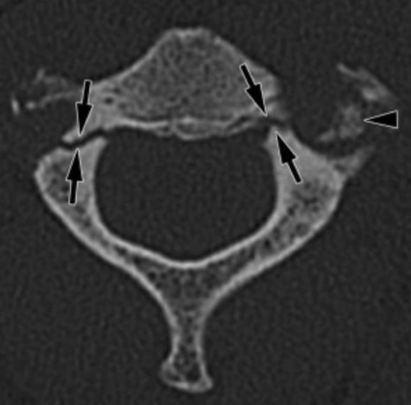

Hangmans fracture- c2 fracture of pars interarticularis

Hyperextension injury